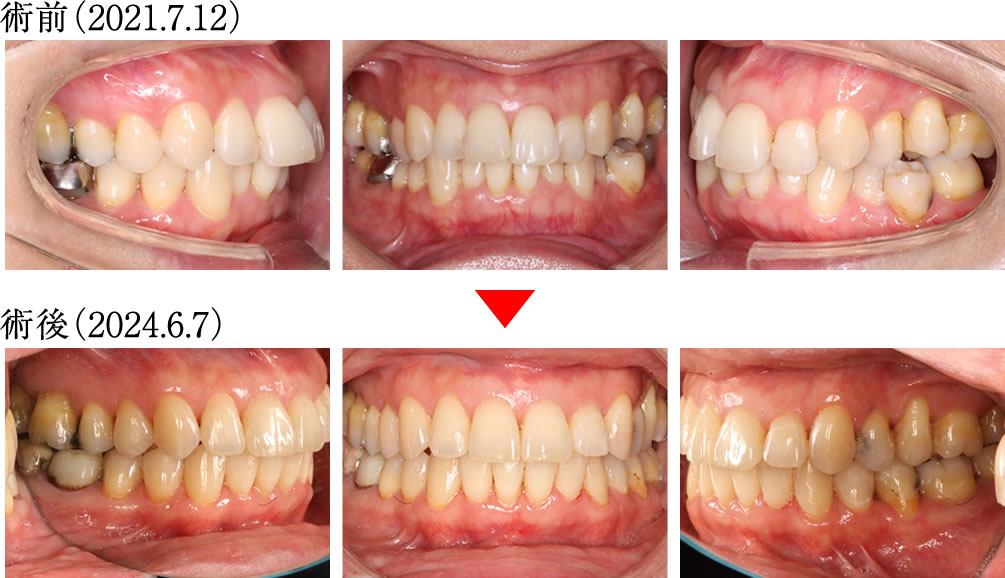

こちらの患者さまは、歯ぎしり・食いしばりによる様々な不調を主訴で来院されました。患者さまと相談し、矯正治療によって歯ぎしり・食いしばりを改善する計画を立てました。

術前は前歯の噛み込みが深く、奥歯も正しく噛み合わない不安定な歯並びでしたが、術後は前歯から奥歯までバランスよく整い、理想的で美しい歯並びへと改善されました。

術前は下顎を動かした際に犬歯が全く機能しておらず、不安定な噛み合わせでしたが、術後は前歯と犬歯が正常に機能するようになり、安定した理想的な咬合へと改善されました。